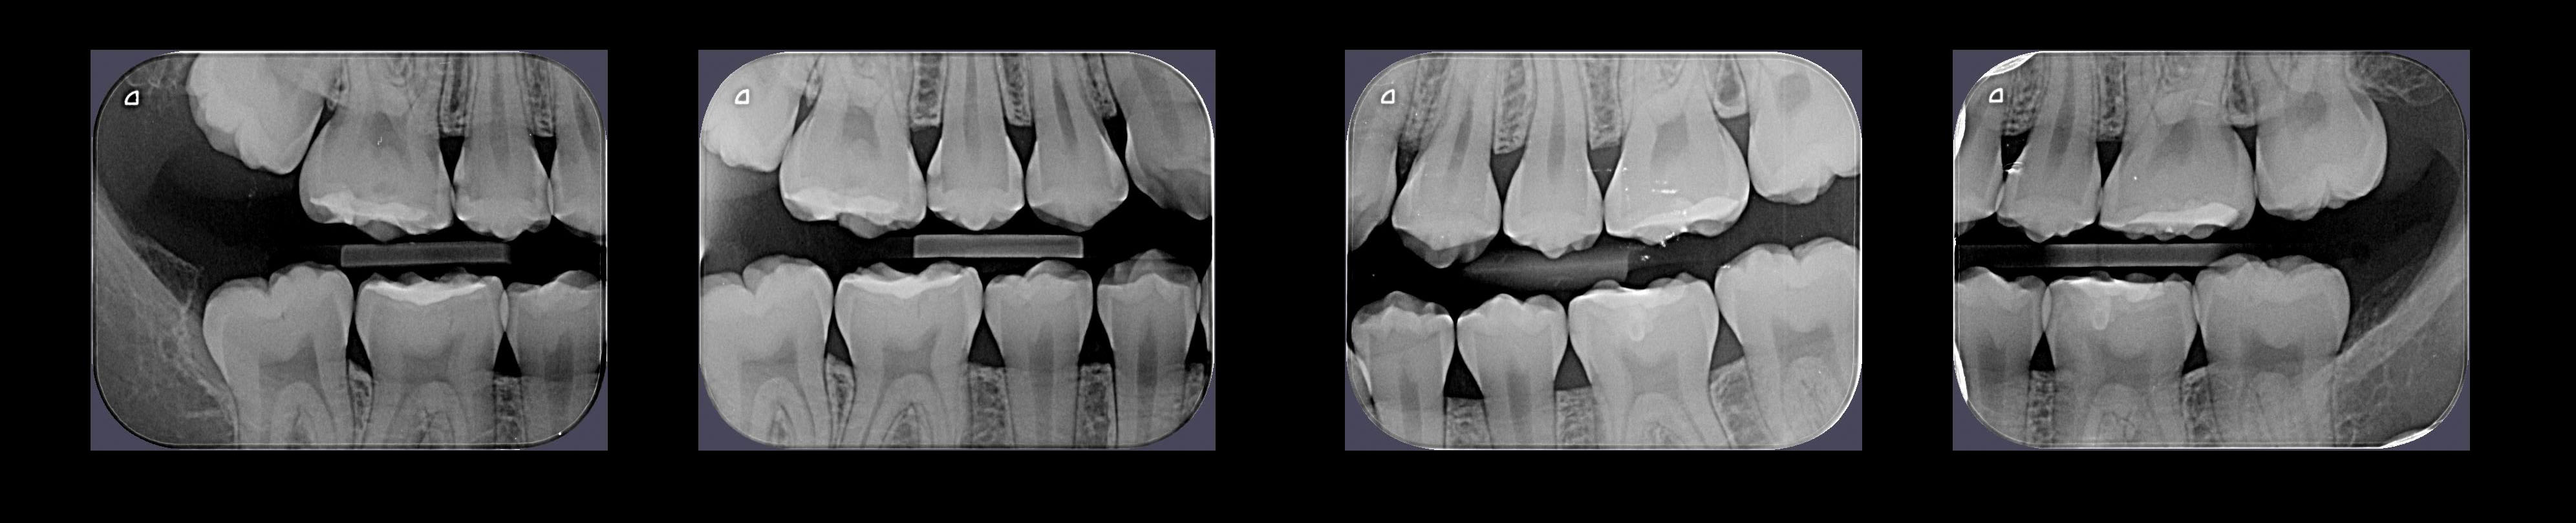

Técnica radiográfica Intrabucal, também chamada de "Bite-wing", que possibilita a visualização das coroas na região de pré-molares e molares.

Principais Indicações:

• Diagnóstico ou detecção de cáries;

• Acompanhamento da progressão das cáries;

• Avaliação pós-traumática dos dentes e do osso alveolar;

• Avaliação das restaurações e próteses instaladas (contornos marginais);

• Avaliação do periodonto;